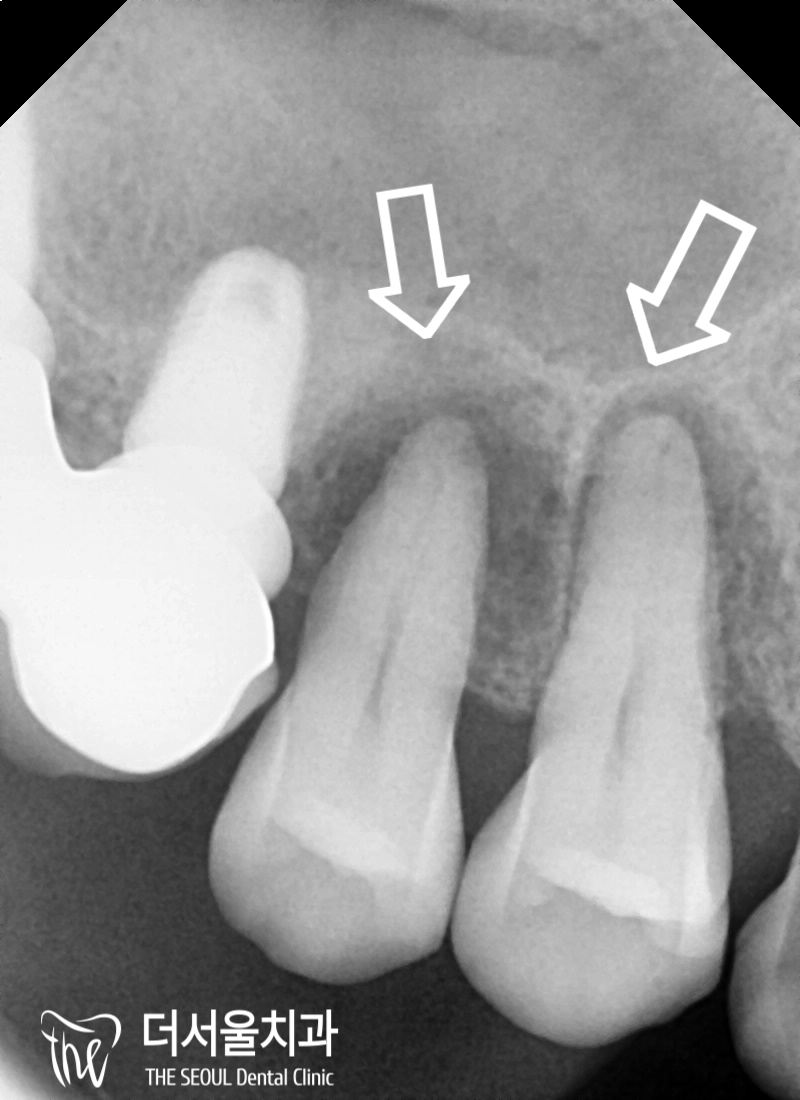

뿌리쪽을 들여다 봤을 때

어둡게 보여지는 ‘염증’ 들도 관찰되었죠.

이런 병소들이 점점 퍼져나가면서

뼈를 녹여서 두께가 얇아진 것입니다.

뿌리 끝이 어두워져 있는 것이 확인되죠?

이것들을 그대로 두면

주위로 계속 퍼져나가게 됩니다.

이에 따라 치조골이 퇴축이 되면

잇몸 또한 같이 내려앉게 되죠.